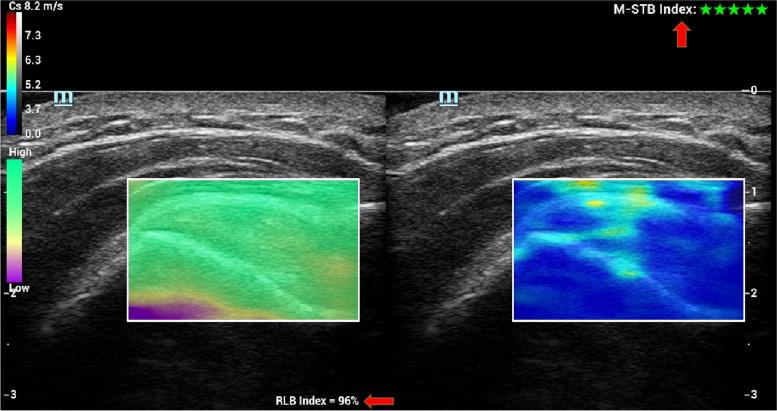

Effective evaluation of rotator cuff tear residual tendon quality is the key to surgical repair. However, until now, the evaluation of rotator cuff tissue by ultrasonic shear wave elasticity (SWE) has been controversial. This prospective study analyzed the association between preoperative SWE and arthroscopic residual tendon quality scores.

The shear wave velocity (SWV) of the deltoid muscle, the supraspinatus tendon, and the supraspinatus muscle were measured in full-thickness rotator cuff tear patients. Tendon quality was scored according to tear size, tendon margin, tendon thickness, and footprint coverage during arthroscopy. The arthroscopic scores were used as the gold standard, and the SWV ratio of tendon and muscle (supraspinatus tendon/deltoid and supraspinatus muscle/deltoid) were calculated and correlated with the arthroscopic scores.

Eighty-nine patients (129 shoulders) were enrolled, including 89 operation shoulders and 40 control shoulders. In the group of operation shoulders, both the SWV ratios of tendon (SWV-RT) and the SWV ratio of muscle (SWV-RM) were negatively correlated with arthroscopic scores (The correlation coefficient (R) ranged from -0.722 to -0.884 and -0.569 to -0.689). The SWV-RT and SWV-RM of the operation shoulders were significantly lower than that of the control shoulders (p < 0.05).

SWE could be used to predict the quality of the residual tendon before the rotator cuff repair. SWV of the supraspinatus tendon and muscle was a useful parameter to predict the quality of the residual tendon.

Measuring the shear wave velocity of the supraspinatus tendon and muscle with SWE is useful for predicting the quality of the residual tendon which is one of the key factors for a successful rotator cuff repair.